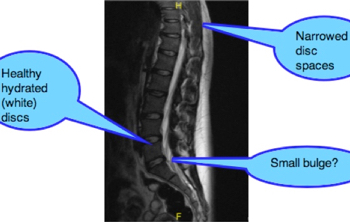

Maigne's syndrome on X-ray.